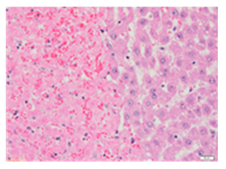

Liver wet weights of all rat groups showed no significant differences (Table 8). According to histochemical hematoxylin and eosin (H&E) staining, treatment with the highest dose of MPE (1000 mg/kg BW) did not result in morphological changes in the liver tissue (B) when compared with DI water treatment (A). Obviously, CCl4 induction (ip)/DI water treatment (po) caused hepatoxicity, which was indicated by a severe degree of fatty changes and fatty cysts in the liver tissue (C), whereas pretreatments of silymarin (100 mg/kg BW, po) effectively decreased the degree of fatty changes and fatty cysts in the liver when compared with the CCl4/DI water group. Indeed, MPE (250 and 1000 mg/kg BW, po) lowered the degree of lipid accumulation in the liver; inversely, MPE (500 mg/kg BW, po) exhibited a severe degree of lipid accumulation. Apparently, taking paracetamol (2 g/kg BW) induced a severe degree of hepatic necrosis when compared with rats that had not received the treatment. Similarly, pretreatments of silymarin (100 mg/kg BW, po) and MPE (250 and 1000 mg/kg BW, po) revealed a mild degree of hepatic necrosis, while MPE (500 mg/kg BW, po) revealed a moderate to severe degree of hepatic necrosis. Accordingly, the findings imply that the consumption of MPE (1000 mg/kg BW) was not harmful to the liver of healthy rats, while MPE (250 mg/kg BW) did improve fat deposition in the livers of CCl4-fed rats and offered protection against liver cell damage in paracetamol-fed rats.

Wet weight values (mean ± SD) and H&E staining of liver from rats with hepatotoxicity induced by CCl4 and paracetamol.

Each liver was embedded in a paraffin block, cut into slides, deparaffinized, and stained with hematoxylin and eosin (H&E) dye. The liver tissue sections were examined in terms of their histopathological status and photographed under light microscopy by a qualified expert clinical pathologist at the Department of Pathology, Faculty of Medicine, Chiang Mai University, Thailand.